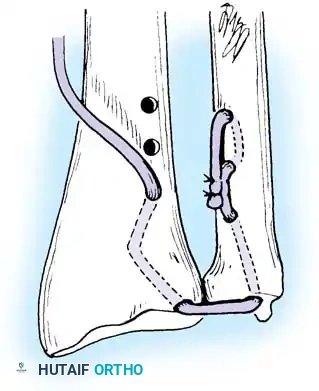

Preparation of the distal ulna: Drill holes are created at the fovea to facilitate transosseous suture passage for anatomic TFCC reattachment.

Transosseous Repair Technique:

1. Identify the foveal detachment arthroscopically or via an open dorsal ulnar approach.

2. Prepare the ulnar fovea down to bleeding bone using a burr or curette to stimulate a healing response.

3. Utilize a targeting guide to drill two converging osseous tunnels from the ulnar neck into the fovea.

Passing non-absorbable sutures through the osseous tunnels in the ulna to capture the peripheral edge of the TFCC.

- Pass strong, non-absorbable sutures (e.g., 2-0 FiberWire) through the TFCC using an outside-in or inside-out technique, then shuttle the suture limbs down the osseous tunnels.

The sutures are tied securely over the cortical bone bridge of the ulnar neck, restoring tension to the radioulnar ligaments.

- Tie the sutures over the ulnar cortical bridge with the forearm in neutral rotation to restore anatomic tension.